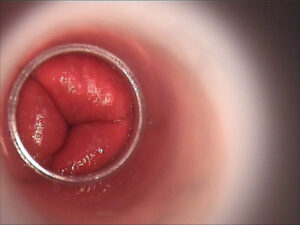

Les hémorroïdes sont des veines dilatées situées dans la région anale et rectale. Elles ressemblent à des varices et peuvent apparaître à l’intérieur du rectum (hémorroïdes internes) ou autour de l’anus (hémorroïdes externes). Cette dilatation des veines provoque une inflammation, une sensation de lourdeur et parfois des saignements.

- Examen clinique de la région anale.

- Toucher rectal pour détecter les hémorroïdes internes.

- Anuscopie ou rectoscopie en cas de saignement important, pour éliminer d’autres causes.

- Hémorroïdes internes : saignement rouge vif lors de la défécation, démangeaisons, sensation de corps étranger dans le rectum.